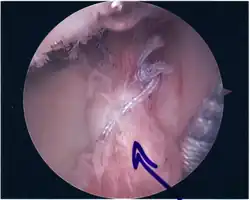

Surgical treatment of SLAP tears has become more common in recent years. The success rate for repairing isolated SLAP tears is reported between 74-94%.[10] While surgery can be performed as a traditional open procedure, an arthroscopic technique[11] is currently favored being less intrusive with low chance of iatrogenic infection.[12]

Following inspection and determination of the extent of injury, the basic labrum repair is as follows.

- The glenoid and labrum are roughened to increase contact surface area and promote re-growth.

- Locations for the bone anchors are selected based on number and severity of tear. A severe tear involving both SLAP and Bankart lesions may require seven anchors. Simple tears may only require one.

- The glenoid is drilled for the anchor implantation.

- Anchors are inserted in the glenoid.

- The suture component of the implant is tied through the labrum and knotted such that the labrum is in tight contact with the glenoid surface.